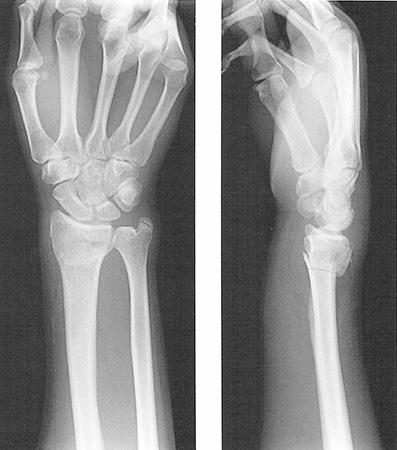

手関節背屈位で手をついて転倒した患者のエックス線単純写真を示す。この病態として正しいのはどれか。